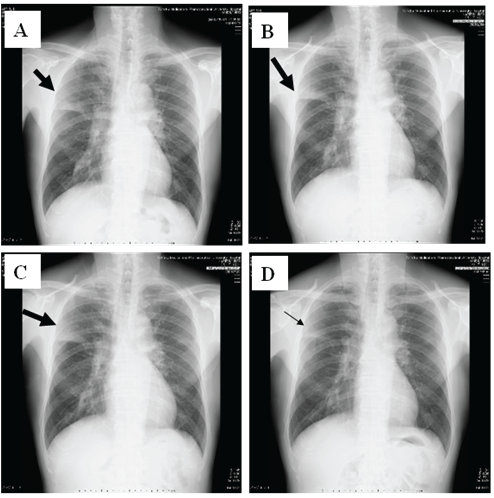

图2:患者的胸部X光改变。分别为A:1天、B:4天、C:7天和D:11天。右上视野的浸润阴影在第1天和第4天没有改变,但在第7天恶化。但是,在使用甲基强的松龙后,在第11天有所改善。

体格检查显示发冷,但无休克(体温38℃⋅7°C;血压120/72 mmHg;心率86 bpm)。根据格拉斯哥昏迷量表,他的意识水平为E3V4M5,右上肺野可听到粗糙的爆裂声和吸气性rhonchi声,他的氧气状态略降至SpO2.:房间空气的95%。确定了5个Curb65严重性项目中的2项。白细胞(WBC)计数为8,300 /μL(中性粒细胞72.3%,嗜酸性粒细胞1.5%,淋巴细胞16.9%,单核细胞8.8%,嗜碱性粒细胞0.5%)。C-反应蛋白水平为6.69mg / dL(图1)。胸部X射线识别右上肺域内的渗透阴影(图2)。

由于怀疑肺炎的免疫机制和/或抗生素的毒性导致肺炎无法缓解,我们从第7天开始静脉注射1mg/kg的甲基强的松龙(mPSL)(图1)。四天后(第11天),他的症状、实验室数据和胸部x光检查结果显著改善,我们停止了mPSL。患者出院后保持健康状况。